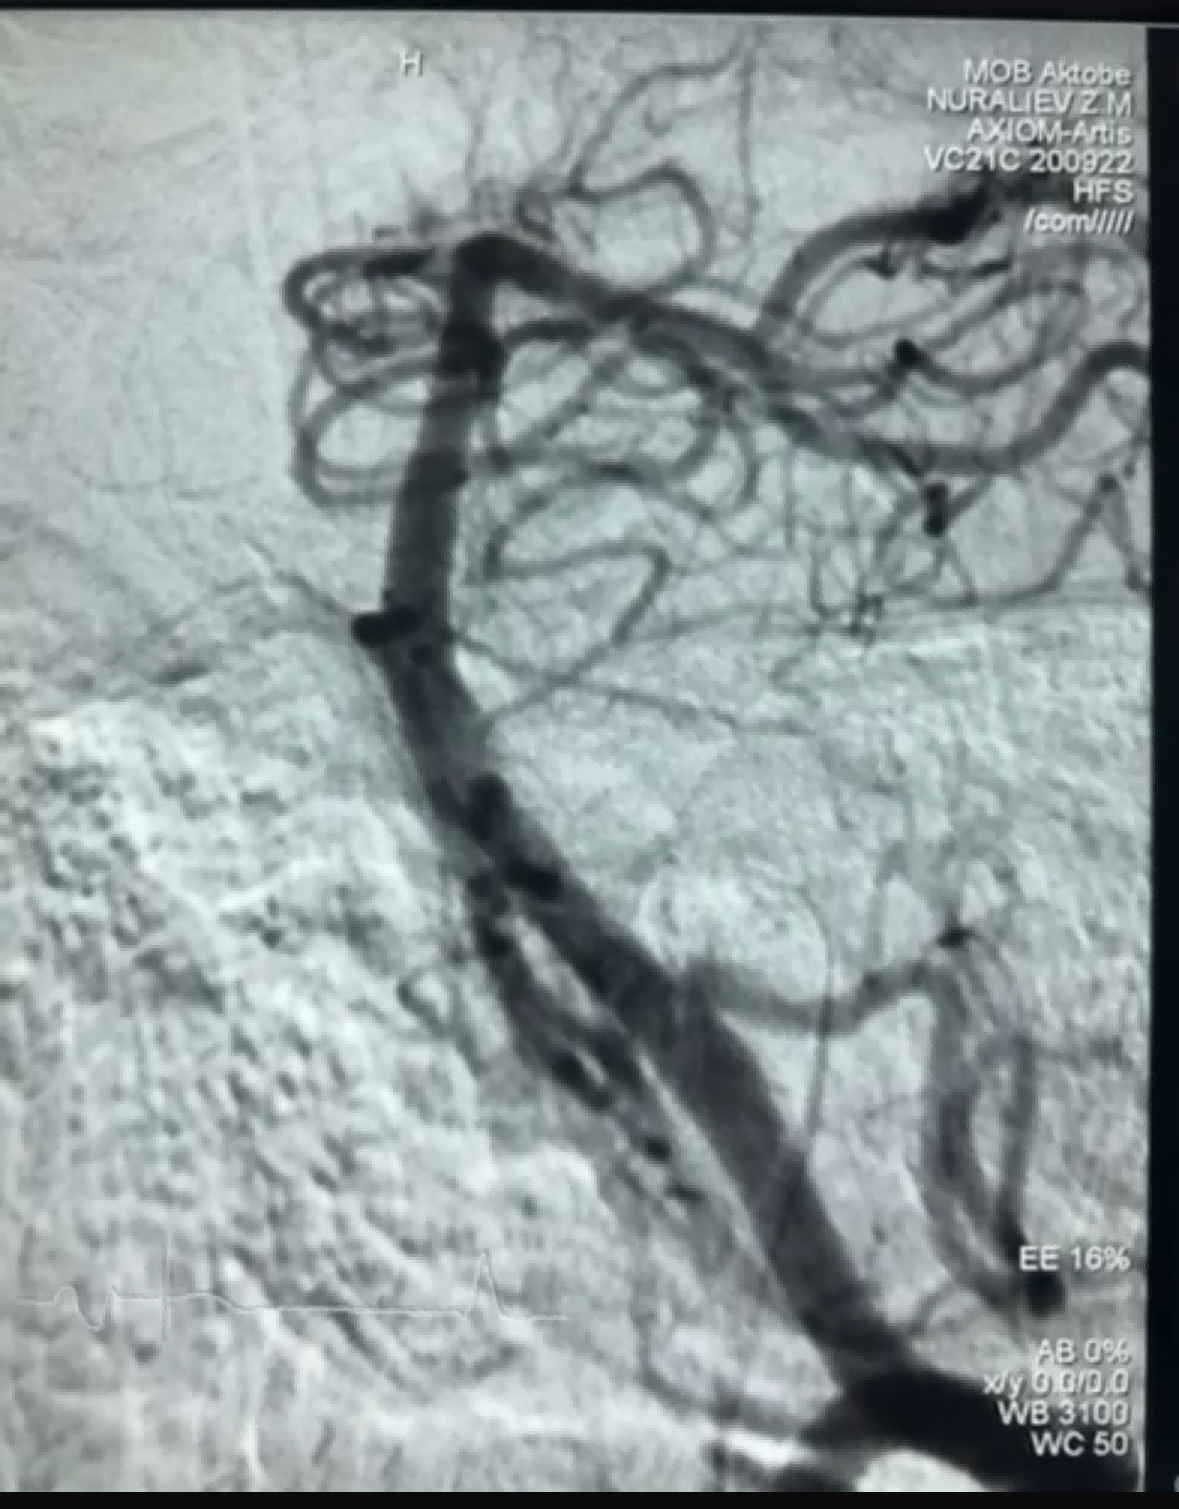

Nyligen inträffade ett framgångsrikt fall av trombektomi med Dredger Stent Retriever från NeuroSafe Medical Co., Ltd. Dredger Stent Retriever har en icke-invasiv mjuk spets, vilket avsevärt minskar risken för intimaskador, och har ett unikt specialformat hål design som fångar upp blodproppar främst genom att klämma fast gapet förändringar.